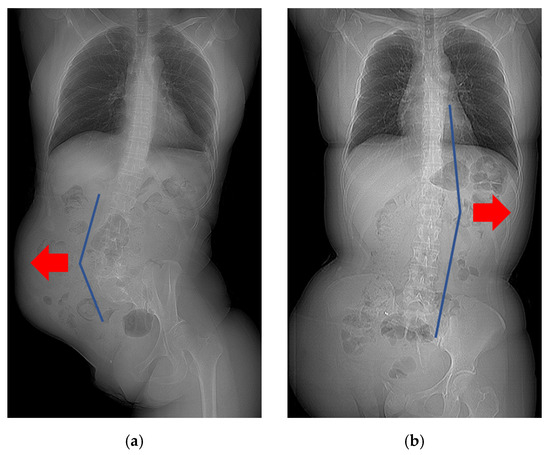

3.4. Factors That Affected the Curve Direction of Scoliosis